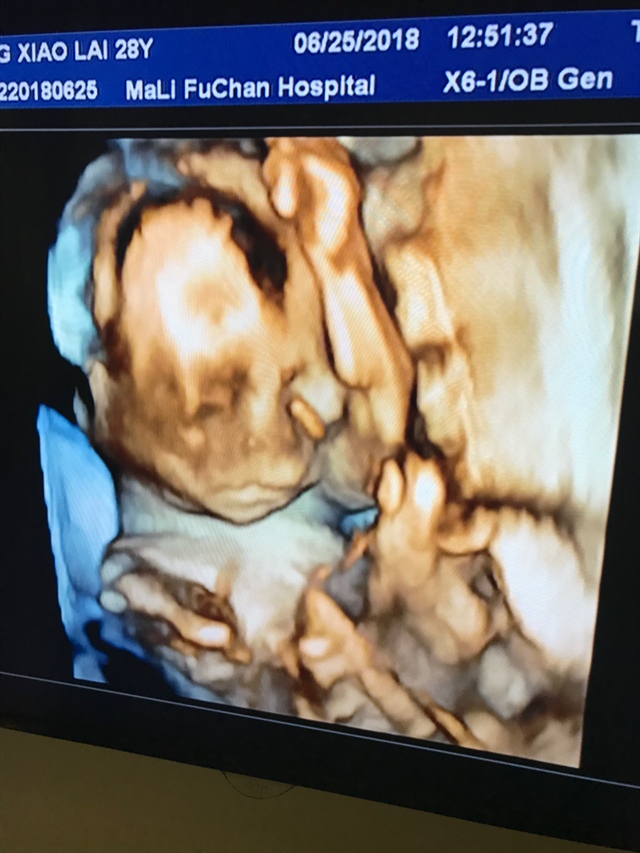

这是几维,画质看着有点恐怖

小小的世界[帖主]:今天做四维,医生不说,男女都一样,不过挺好奇